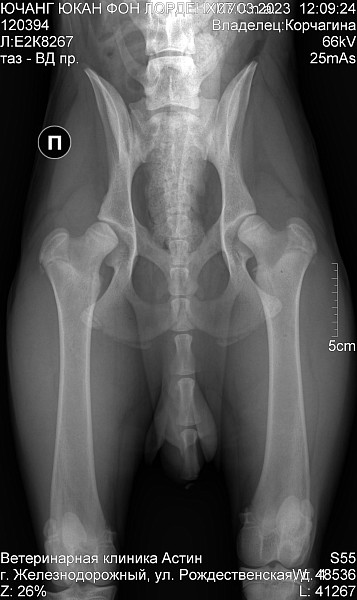

Немецкая овчарка. Кобель.

Др 29 07 2022

С первого дня дома бегал как заяц, на первых прогулках подтвердился такой бег. С трудом встаёт, перенося вес на передние лапы. Хромает спустя 10 минут прогулки.

Врачи в городе не дают внятных ответов и заключений. Хочется узнать имеется ли на снимке дисплазия?

Добрый день. Двустороння дисплазия тазобедренных суставов. Рекомендован прием ортопеда и имплантация суставов